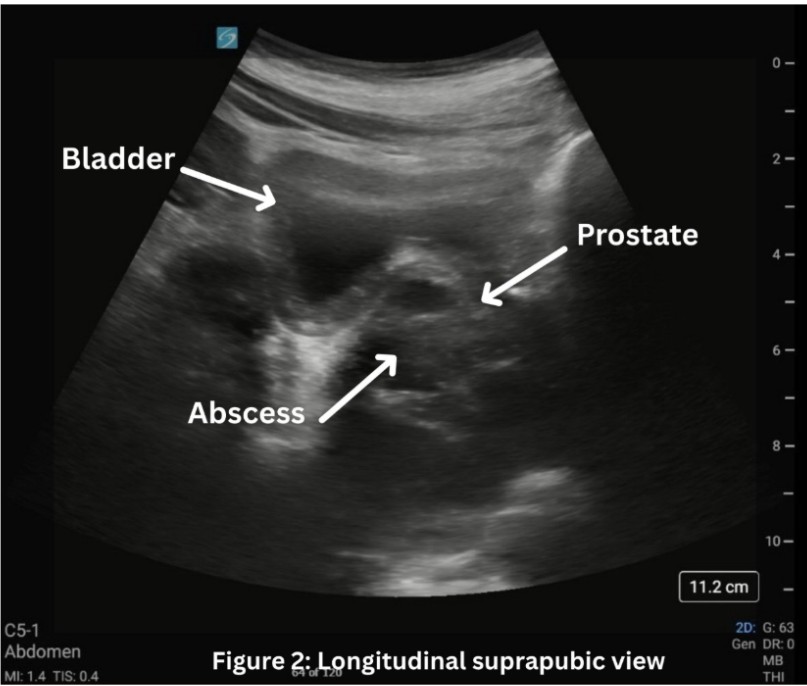

In our patient’s case, the use of point of care transabdominal ultrasound to investigate the patient’s sensation of urinary retention led to the preliminary diagnosis of PA. On ultrasound, in both the transverse (1) and longitudinal (2) view, a multiloculated abscess is seen, indicated by the hypoechoic areas, measuring approximately 5 x 5 x 5 cm. CT scan was then done to confirm and better characterize the abscess, urology was consulted, and ultimately the patient had definitive treatment with antibiotics and transurethral unroofing of the abscess in the operating room.

Figure 1: Transverse view of the bladder with prostate abscess.

Figure 2: Longitudinal view of the bladder with prostate abscess.